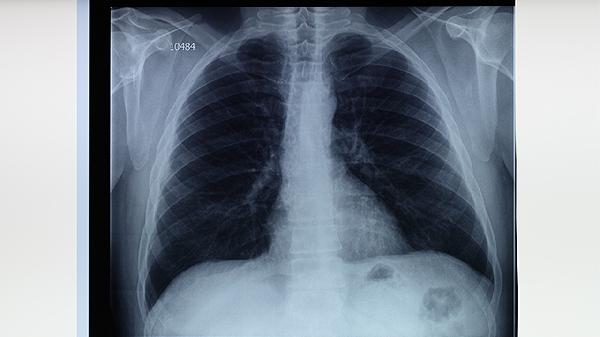

婴幼儿结核病可通过结核菌素试验、胸部X线检查、痰涂片镜检、γ-干扰素释放试验等方式检查。 1、结核菌素试验: 通...